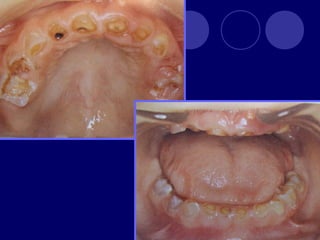

DENTINOGENESIS IMPERFECTA TIPO I:asociada a padecimiento esquelético, asociada a osteogénesis imperfecta (escleróticas azules, sordera, múltiples fracturas,etc.)  Dos denticiones  Dientes blandos, consistencia terrosa  Rx: cámaras pulpares obliteradas

TIPO II:  Dientesde color: amarillo, pardo azulado u opalescente con brillo translúcido, raíces color ámbar  Rx: coronas bulbosas, cámaras pequeñas o ausentes, raíces delgadas y cortas TIPO III: (SHIELDS)  Temporal: translúcido, ámbar  Permanente: normal

OSTEOGENESIS IMPERFECTA Alteración deesmalte y dentina En la dentición temporal no hay esmalte y dentina muy abrasionada En la dentición permanente esmalte frágil color grisáceo y amplias zonas desprovistas de éste, dentina atípica